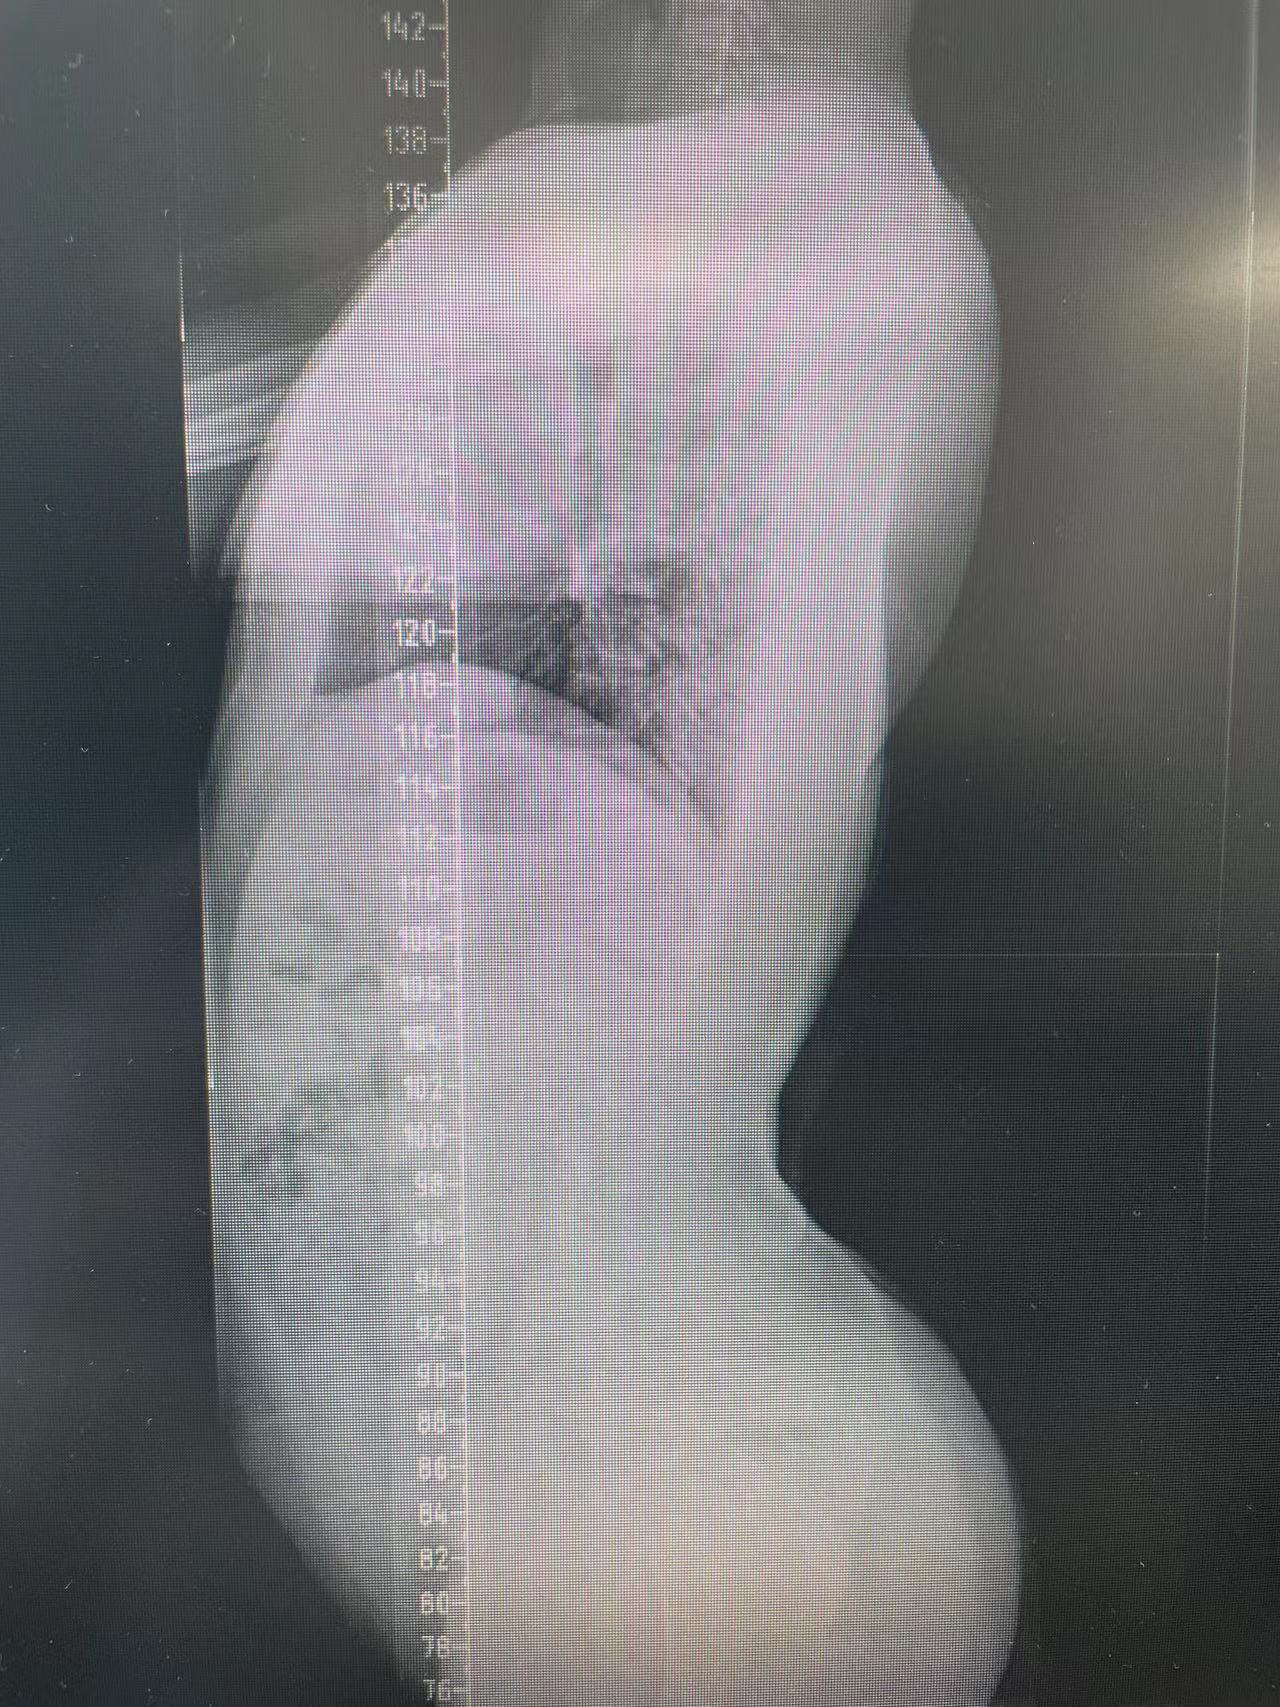

患者杨某,15岁,一年前在家中行走不稳,未及时给予系统治疗,现双下肢僵硬、无力症状明显,影响正常生活,遂前来91直播 脊柱外科中心D区接受住院治疗。

脊柱外科中心D区辛大奇、王东海、孙洪岩医疗团队完善患者术前检查后,明确诊断为胸12半椎体侧后凸畸形,经过积极与胡侦明教授沟通、讨论后,共同为患者制定手术方案,为患者施行先天性脊柱侧弯、半椎体侧后凸畸形截骨矫形+植骨融合内固定术。